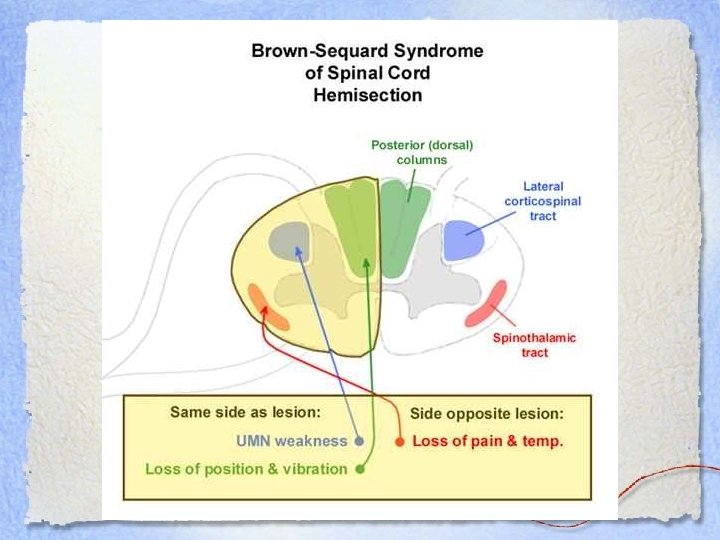

Brown-Séquard Syndrome • Hemisection of the cord • Ipsilateral loss of: – Motor function – Proprioception and vibration sense • Contralateral loss of: – Pain and temperature sensation

Brown-Séquard Syndrome • Hemisection of the cord • Ipsilateral loss of: – Motor function – Proprioception and vibration sense • Contralateral loss of: – Pain and temperature sensation

BSS • Caused by: – Penetrating injury – Lateral cord compression from: • • Disk protrusion Hematomas Bone injury Tumours • Prognosis: GOOD

BSS • Caused by: – Penetrating injury – Lateral cord compression from: • • Disk protrusion Hematomas Bone injury Tumours • Prognosis: GOOD